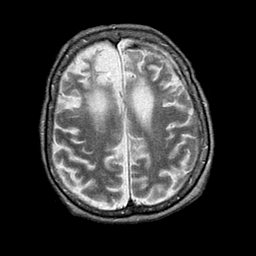

Pick's Disease, MR Study mr-t2 -- Slice #16

[Home][Help][Clinical] Slice 16